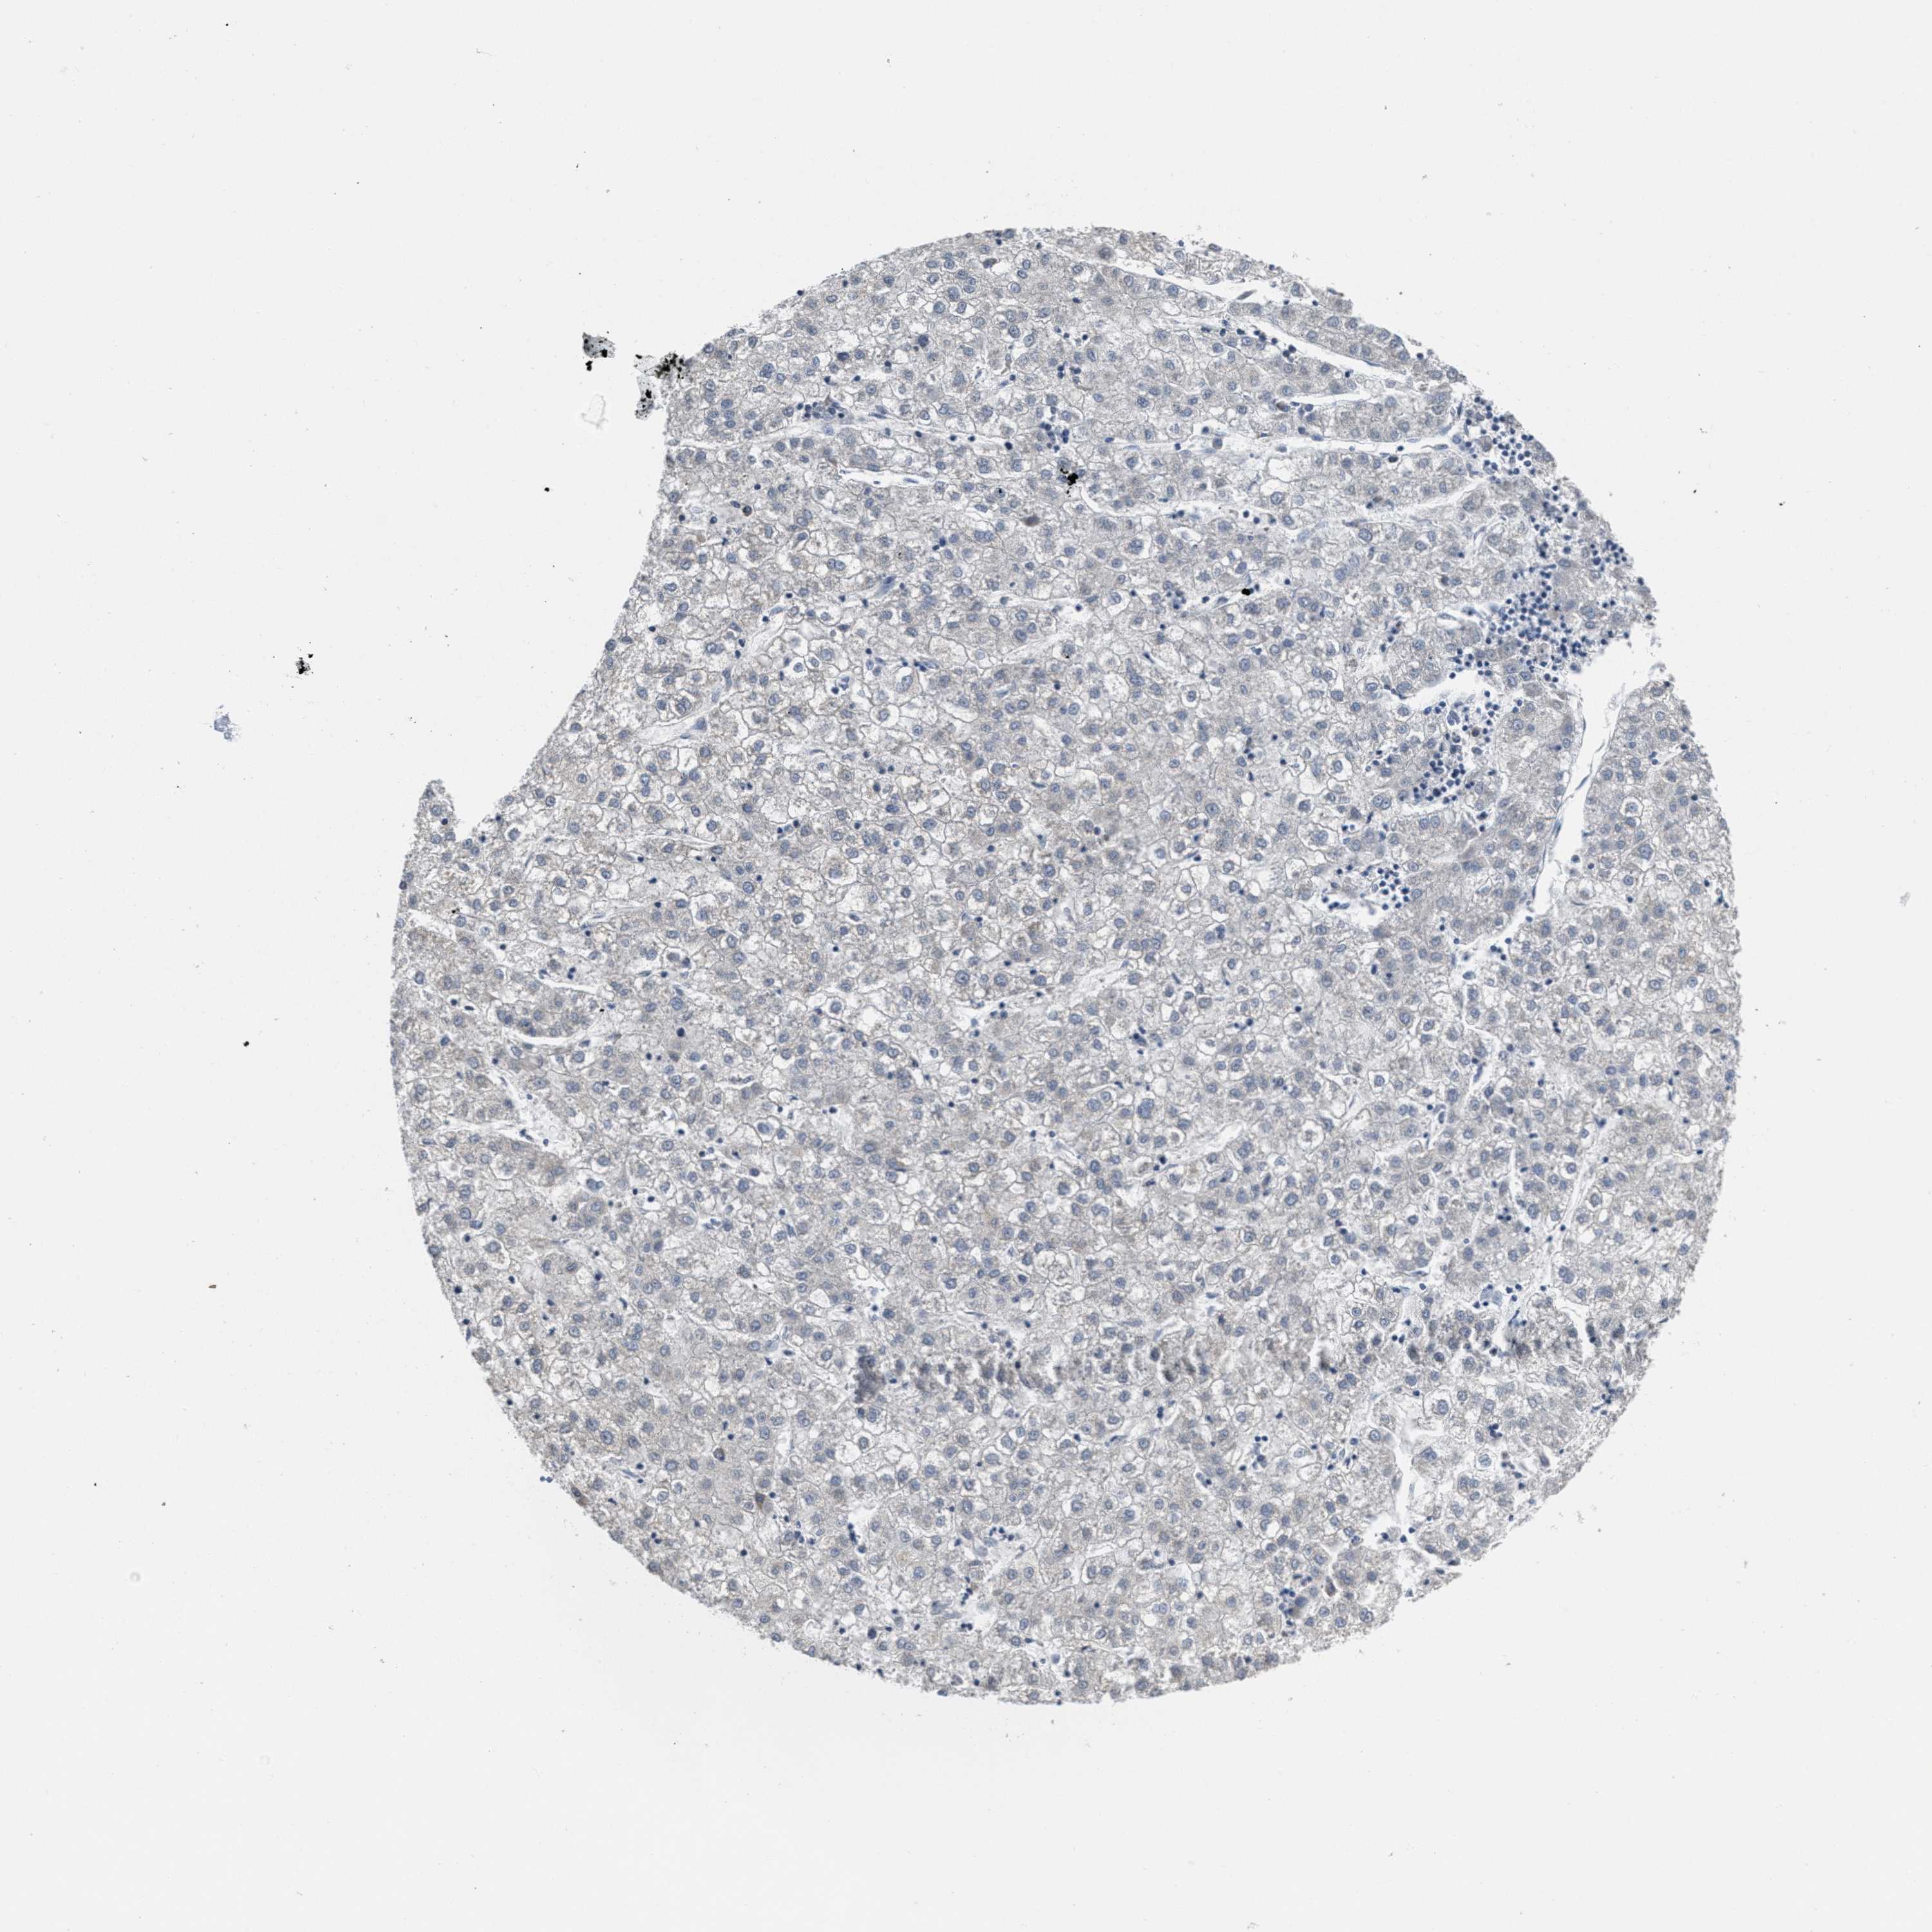

LIVER CANCER - Protein expressioni

A mouse-over function shows sample information and annotation data. Click on an image to view it in a full screen mode. Samples can be filtered based on level of antibody staining by selecting one or several of the following categories: high, medium, low and not detected. The assay and annotation is described here.

Note that samples used for immunohistochemistry by the Human Protein Atlas do not correspond to samples in the TCGA dataset.

Antibody stainingi

Antibody staining in the annotated cell types in the current human tissue is reported as not detected, low, medium, or high, based on conventional immunohistochemistry profiling in selected tissues. This score is based on the combination of the staining intensity and fraction of stained cells.

Each image is clickable and will lead to virtual microscopy that enables deeper exploration of all samples and also displays staining intensity scores, fraction scores and subcellular localization as well as patient and tissue information for each sample.

Antibody HPA018793

Antibody HPA018816

Antibody CAB017815

Staining

High

Medium

Low

Not detected

Intensity

Strong

Moderate

Weak

Negative

Quantity

>75%

75%-25%

<25%

None

Location

Nuclear

Cytoplasmic/membranous

Cytoplasmic/membranous,nuclear

Carcinoma, Hepatocellular, NOS

Cholangiocarcinoma